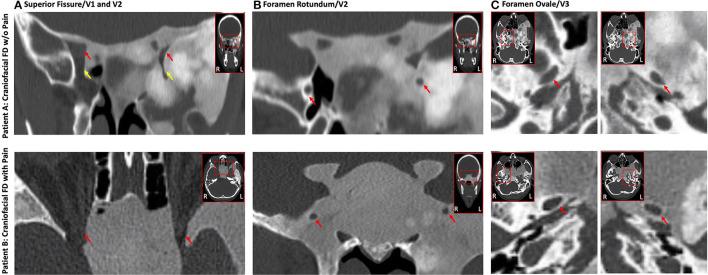

Patients with fibrous dysplasia (FD) often present with craniofacial lesions that affect the trigeminal nerve system. Debilitating pain, headache, and migraine are frequently experienced by FD patients with poor prognosis, while some individuals with similar bone lesions are asymptomatic. The clinical and biological factors that contribute to the etiopathogenesis of pain in craniofacial FD are largely unknown. We present two adult females with comparable craniofacial FD lesion size and location, as measured by F-sodium fluoride positron emission tomography/computed tomography (PET/CT), yet their respective pain phenotypes differed significantly. Over 4 weeks, the average pain reported by Patient A was 0.4/0-10 scale. Patient B reported average pain of 7.8/0-10 scale distributed across the entire skull and left facial region. Patient B did not experience pain relief from analgesics or more aggressive treatments (denosumab). In both patients, evaluation of trigeminal nerve divisions (V1, V2, and V3) with CT and magnetic resonance imaging (MRI) revealed nerve compression and displacement with more involvement of the left trigeminal branches relative to the right. First-time employment of diffusion MRI and tractography suggested reduced apparent fiber density within the cisternal segment of the trigeminal nerve, particularly for Patient B and in the left hemisphere. These cases highlight heterogeneous clinical presentation and neurobiological properties in craniofacial FD and also, the disconnect between peripheral pathology and pain severity. We hypothesize that a detailed phenotypic characterization of patients that incorporates an advanced imaging approach probing the trigeminal system may provide enhanced insights into the variable experiences with pain in craniofacial FD.

骨纤维异常增殖症(FD)患者常出现影响三叉神经系统的颅面病变。预后较差的FD患者经常经历使人衰弱的疼痛、头痛和偏头痛,而一些有类似骨病变的个体却没有症状。导致颅面FD疼痛的病因发病机制的临床和生物学因素在很大程度上尚不清楚。我们报告了两名成年女性,通过氟[¹⁸F]氟化钠正电子发射断层扫描/计算机断层扫描(PET/CT)测量,她们的颅面FD病变大小和位置相当,但各自的疼痛表型却有显著差异。在4周的时间里,患者A报告的平均疼痛为0.4/0 - 10分制。患者B报告的平均疼痛为7.8/0 - 10分制,疼痛分布在整个颅骨和左面部区域。患者B使用镇痛药或更积极的治疗(地诺单抗)后疼痛并未缓解。对两名患者进行CT和磁共振成像(MRI)评估三叉神经分支(V1、V2和V3)时发现神经受压和移位,相对于右侧,左侧三叉神经分支受累更多。首次使用扩散MRI和神经纤维束成像显示三叉神经脑池段内的表观纤维密度降低,尤其是患者B和左侧半球。这些病例突出了颅面FD的异质性临床表现和神经生物学特性,也表明了周围病理与疼痛严重程度之间的脱节。我们推测,对患者进行详细的表型特征描述,并采用先进的成像方法探测三叉神经系统,可能会为深入了解颅面FD患者疼痛的不同体验提供更多见解。